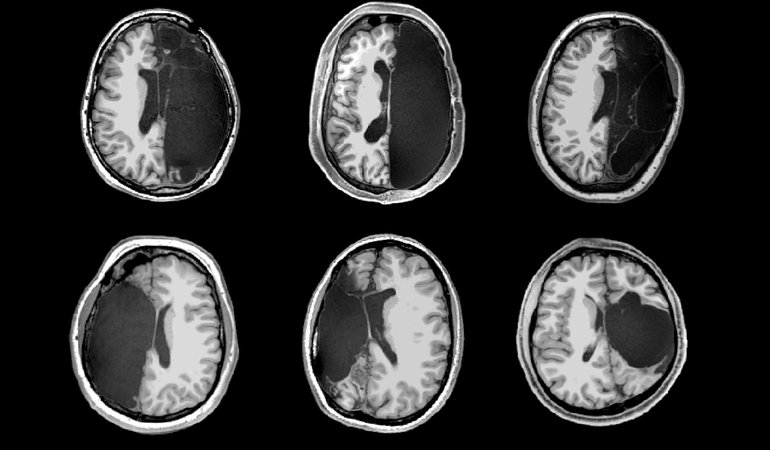

Structural images from a Caltech investigation of six of rare hemispherectomy patients, all of whom received the surgeries as children and now have relatively normal cognitive abilities. Brain networks in these patients - controlling walking, talking, and other functions - were remarkably intact. This study, published in Cell Reports [https://resolver.caltech.edu/CaltechAUTHORS:20191119-095728876] was funded by The Brain Recovery Project: Childhood Epilepsy Surgery Foundation, the National Institutes of Health, and the National Science Foundation.